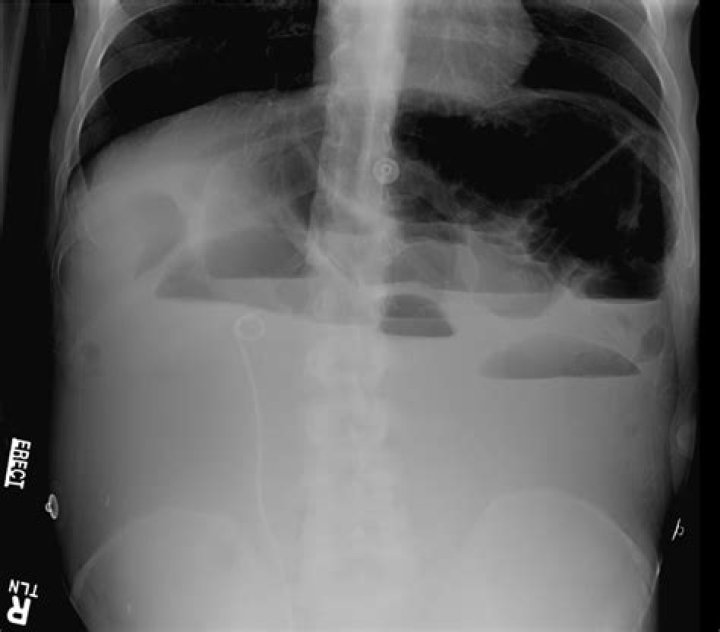

A kidney, ureter, and bladder (KUB) X-ray is also known as a “flat plate of the abdomen x-ray,” may be performed to assess the abdominal area for causes of abdominal pain, or to assess the organs and structures of the urinary and/or gastrointestinal (GI) system.

: a radiograph especially of the abdomen taken with the subject lying flat.